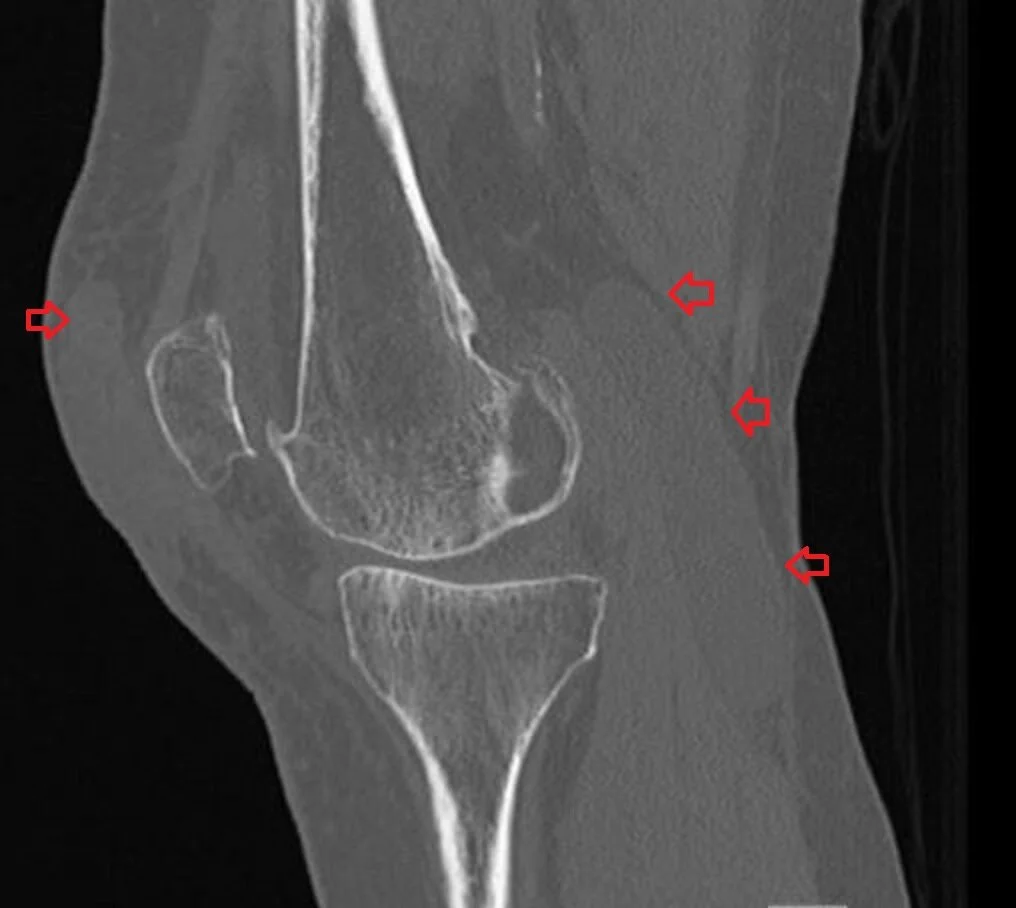

From www.everydayebm.org

A 73 y.o. woman comes in after a fall and has severe knee pain Baker's Cyst Dvt Other common baker cyst symptoms include: what is a baker’s cyst? A ruptured baker's cyst cannot be. Similar symptoms of baker’s cyst, popliteal vein thrombosis, and dvt. The pain can get worse when with. Deep vein thrombosis (dvt) is a serious condition that happens. symptoms and causes. What are baker cyst symptoms? A baker cyst can often be. Baker's Cyst Dvt.